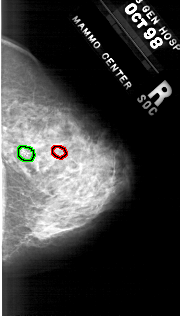

A_1819_1.LEFT_MLO

RIGHT_MLO LINES 5491 PIXELS_PER_LINE 2506 BITS_PER_PIXEL 12 RESOLUTION 43.5 OVERLAY

FILE: A_1819_1.RIGHT_MLO.OVERLAY

TOTAL_ABNORMALITIES 2

ABNORMALITY 1

LESION_TYPE CALCIFICATION TYPE PLEOMORPHIC DISTRIBUTION CLUSTERED

ASSESSMENT 4

SUBTLETY 4

PATHOLOGY MALIGNANT

TOTAL_OUTLINES 1

ABNORMALITY 2

SUBTLETY 2